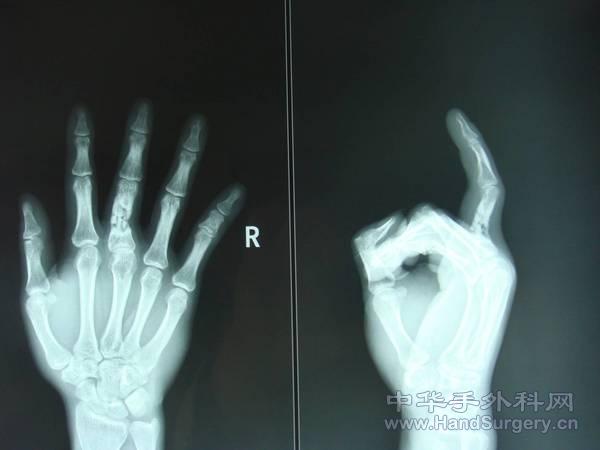

近节指骨粉碎性骨折,骨折块细小